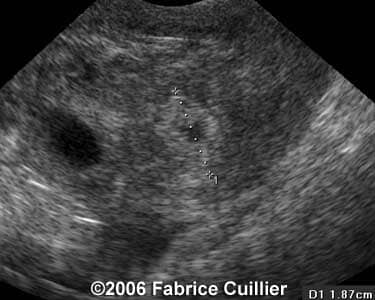

Case 2

case16a

case2a